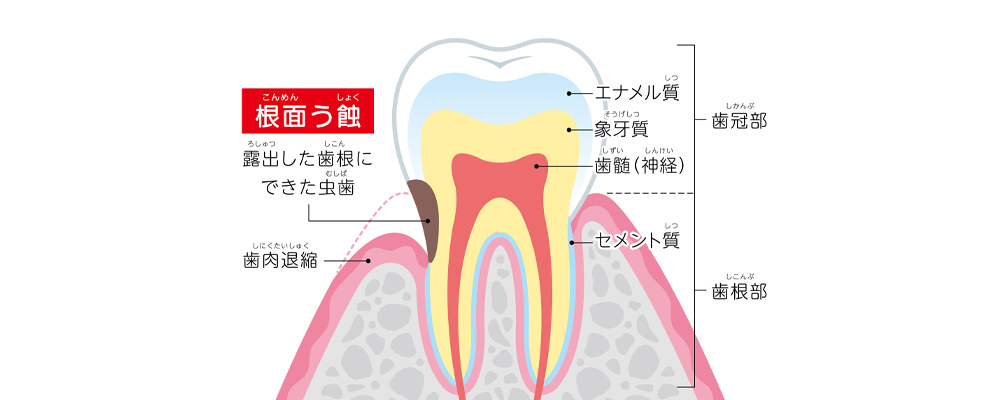

30代からリスクあり!露出した“歯の根元”にできる虫歯

「根面う蝕」は加齢などの影響で歯ぐきが下がり、歯の根の部分(根面)が露出したところにできる虫歯です。通常の虫歯はエナメル質から始まりますが、根面う蝕はエナメル質が存在しない部位に起こります。特に歯の根元は酸に対する抵抗力が弱いため非常に虫歯になりやすく、進行も早いため、歯を失うリスクが高い虫歯です。

【特長】

- 歯ぐきが下がって歯の根の部分が露出したところにできる

- 30代からリスクがある

- 歯の根元は酸に弱く虫歯になりやすい

- 気づきにくく進行しやすい

- 治療しにくいため歯を失うリスクが高い

特に、歯周病がある方や、口が乾きやすい方(ドライマウス傾向の方)はリスクが高まります。